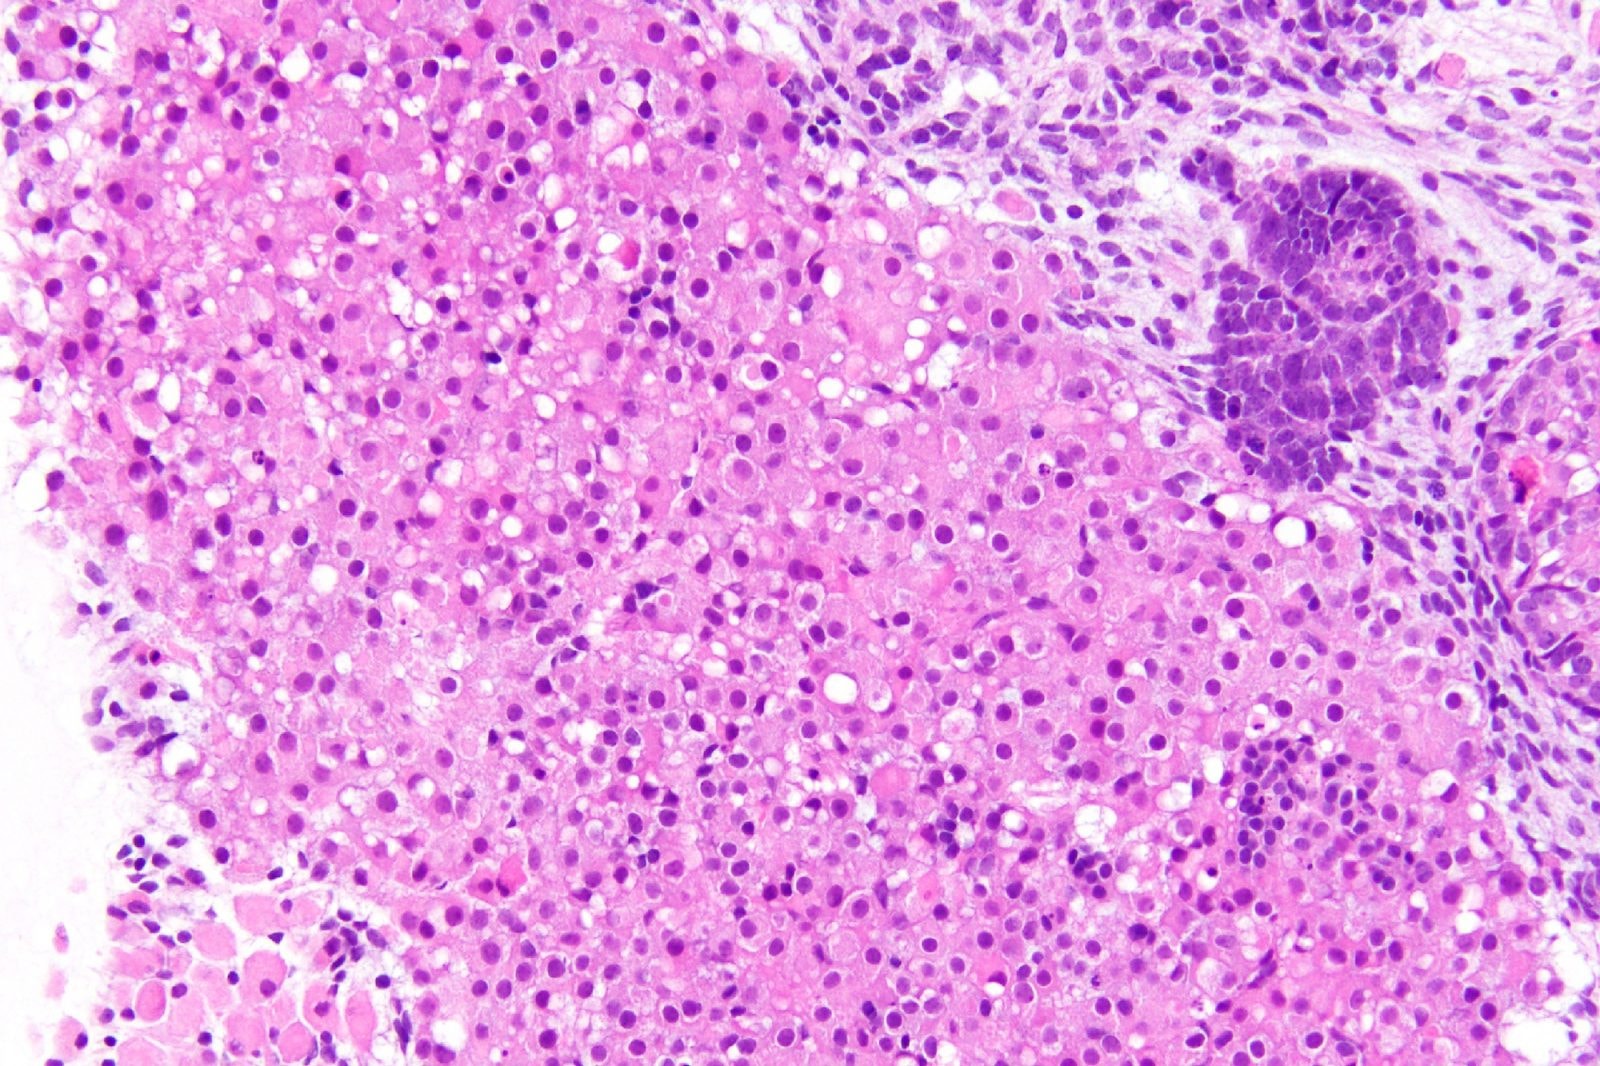

Opracowany przez nas proces był bardzo wydajny, a około 50 proc. komórek w organoidach nabyło cechy komórek nadnercza. Owalne komórki z obszerną różową cytoplazmą i stosunkowo małymi jądrami, które widzieliśmy w naszych hodowlach, są bardzo charakterystyczne dla ludzkich komórek nadnerczy na tym etapie.